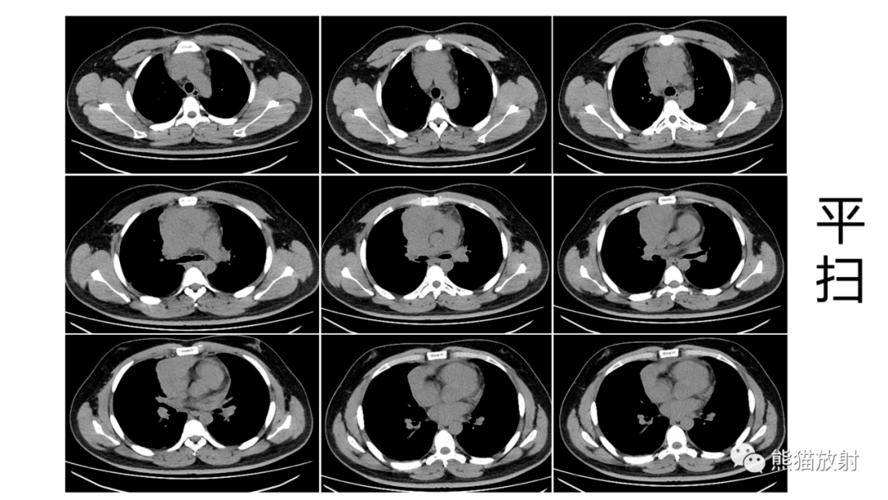

胸腺瘤前纵隔占位前纵隔结节是癌症吗

省立影像读片前纵隔肿瘤2109